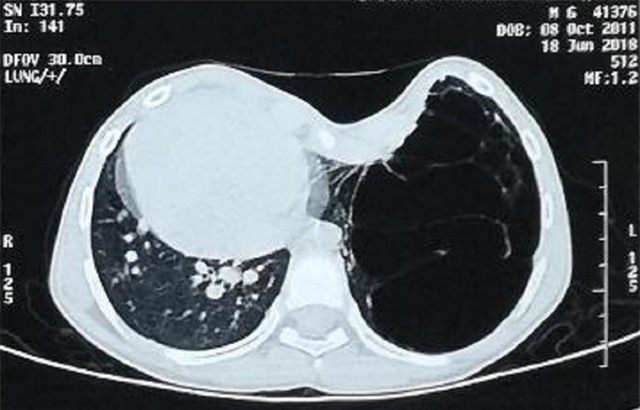

Nang tuyến phổi khổng lồ chiếm gần hết lồng ngực trái của bệnh nhi. |

Đó là trường hợp bé trai N.M.B.Q. (7 tuổi, ngụ tỉnh Đắk Lắk). Từ khi chào đời bé đã bị dị tật ngực lõm, thời gian gần đây bệnh nhi có biểu hiện khó thở, tức ngực, mệt nhiều nên gia đình đưa đến Bệnh viện Nhi đồng 2 thăm khám.

Qua các kết quả kiểm tra, bác sĩ phát hiện bệnh nhi bị dị dạng nang tuyến phổi rất lớn chiếm gần hết phổi trái, đẩy lệch tim sang hẳn lồng ngực bên phải. Nguy hiểm hơn, tình trạng lõm ngực nặng với chỉ số Haller là 4,5 (thông thường chỉ khoảng 3) khiến bệnh nhi đối mặt với nhiều nguy cơ biến chứng nguy hiểm như chèn ép tim và trung thất, cản trở chức năng hô hấp, viêm phổi nặng… nguy cơ tử vong nếu trì hoãn can thiệp sớm.

Bệnh nhi có tổn thương ở thùy dưới phổi trái rất to và viêm dính nhiều vào thành ngực. Sau hội chẩn bệnh viện quyết định phối hợp liên chuyên khoa thực hiện cuộc phẫu thuật khẩn cắt thùy phổi qua phương pháp nội soi đồng thời nâng ngực lõm cho bệnh nhi. Sau 4 tiếng khẩn trương, các bác sĩ đã thực hiện thành công phương pháp cắt thùy phổi bằng nội soi và đặt dụng cụ nâng lồng ngực cho bệnh nhi. Ngày 28/8, hơn 1 tuần sau phẫu thuật can thiệp bệnh nhi hết mệt, ăn uống tốt, tối ngủ ngon.

BS Phạm Ngọc Thạch - Phó giám đốc bệnh viện - cho hay: Dị dạng nang tuyến phổi bẩm sinh có tần suất khoảng 1/12000, còn dị tật lõm ngực có tần suất vào khoảng 1/1000. Tuy nhiên 2 dị tật phối hợp cùng một lúc là trường hợp rất hiếm. Cuộc mổ giải quyết dứt điểm cả 2 bệnh rất khó, chưa nhiều trung tâm trên thế giới có thể thực hiện.